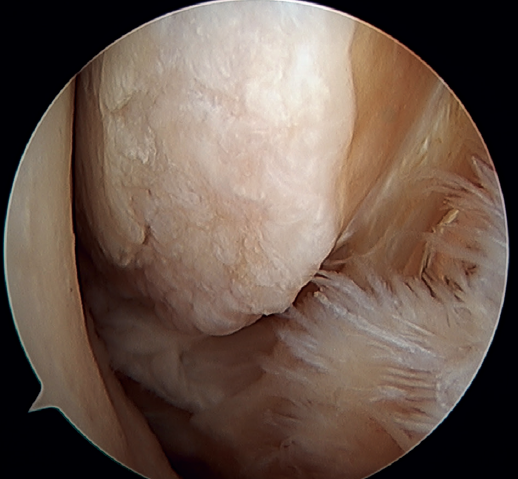

Rotational instability is a relatively novel concept introduced in 2011 by Buchhorn(67), describing combined injuries of the lateral complex and deltoid ligament, and an anatomical reconstruction technique for both injuries. Although there is no biomechanical evidence as to why medial injury occurs in patients who have not suffered eversion trauma, it is likely that the stress maintained on the medial complex in lateral instability may evolve into rotational instability - which is in line with the previously commented domino effect theory (5,62). It is estimated that up to 10-15% of all cases of CLAI may progress to injury of the medial complex, especially affecting its most anterior fibers. Recently, Vega(68) described the combination of injuries of the lateral complex with the "book-page" injury (Figure 7) of the superficial tibiotalar fascicle of the deltoid ligament, due to excessive internal rotation in chronic lateral instability, and its treatment through direct repair of both lesions. Acevedo(34) and Vega(68) also described the safety position of the anchors in the medial malleolus.